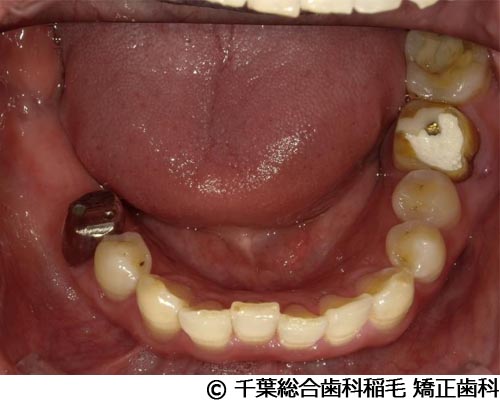

【症例1】下顎大臼歯3本インプラント埋入手術

- 治療前

- 治療後

- 治療名

- 下顎大臼歯3本インプラント埋入手術

- 費用

- 1,400,000円(税込)

- 期間

- 10ヵ月

治療内容

-

患者様の症状

左下第一大臼歯は他院で治療中でしたが、治療がなかなか進まず、他の部位にもお痛みが続いていたため、当院にご相談に来られました。

治療法

左下第一大臼歯は保存が厳しい状態だったため、抜歯となりました。

ご来院時から欠損状態だった右下第一、第二大臼歯も含め、欠損補綴についてお話させていただき、インプラントでの治療を選択されました。 -

治療結果

お痛みも和らぎ、現在も定期検診で拝見させていただいています。

※治療結果は患者様によって個人差があります。